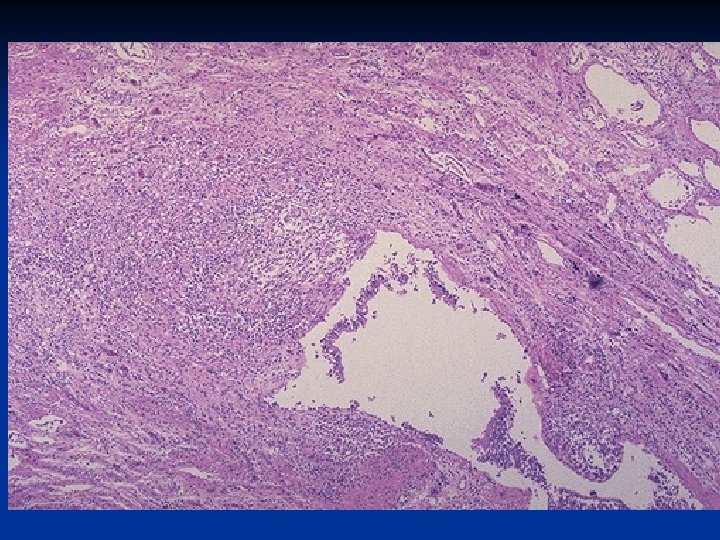

Basic Mechanism: : n Hypersecretion of mucus n Histology -Increased numbers of goblet cells in small airways as well as large airways. -Increased size of submucosal glands in large airways (Reid index: ratio of thickness of mucosal glands to thickness of wall between epithelium and cartilage) -Peribronchiolar chronic inflammation.